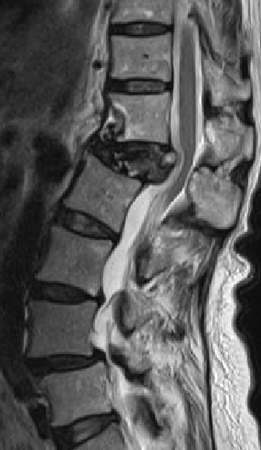

術前MRIでは腰椎椎間板ヘルニアを認め、神経の圧迫を認めています。後方からのヘルニア摘出術により神経症状は劇的に改善しました。

術前MRIでは脊柱管の狭窄を認め、神経の圧迫を認めています。後方からの除圧術後、神経への圧迫は改善しています。